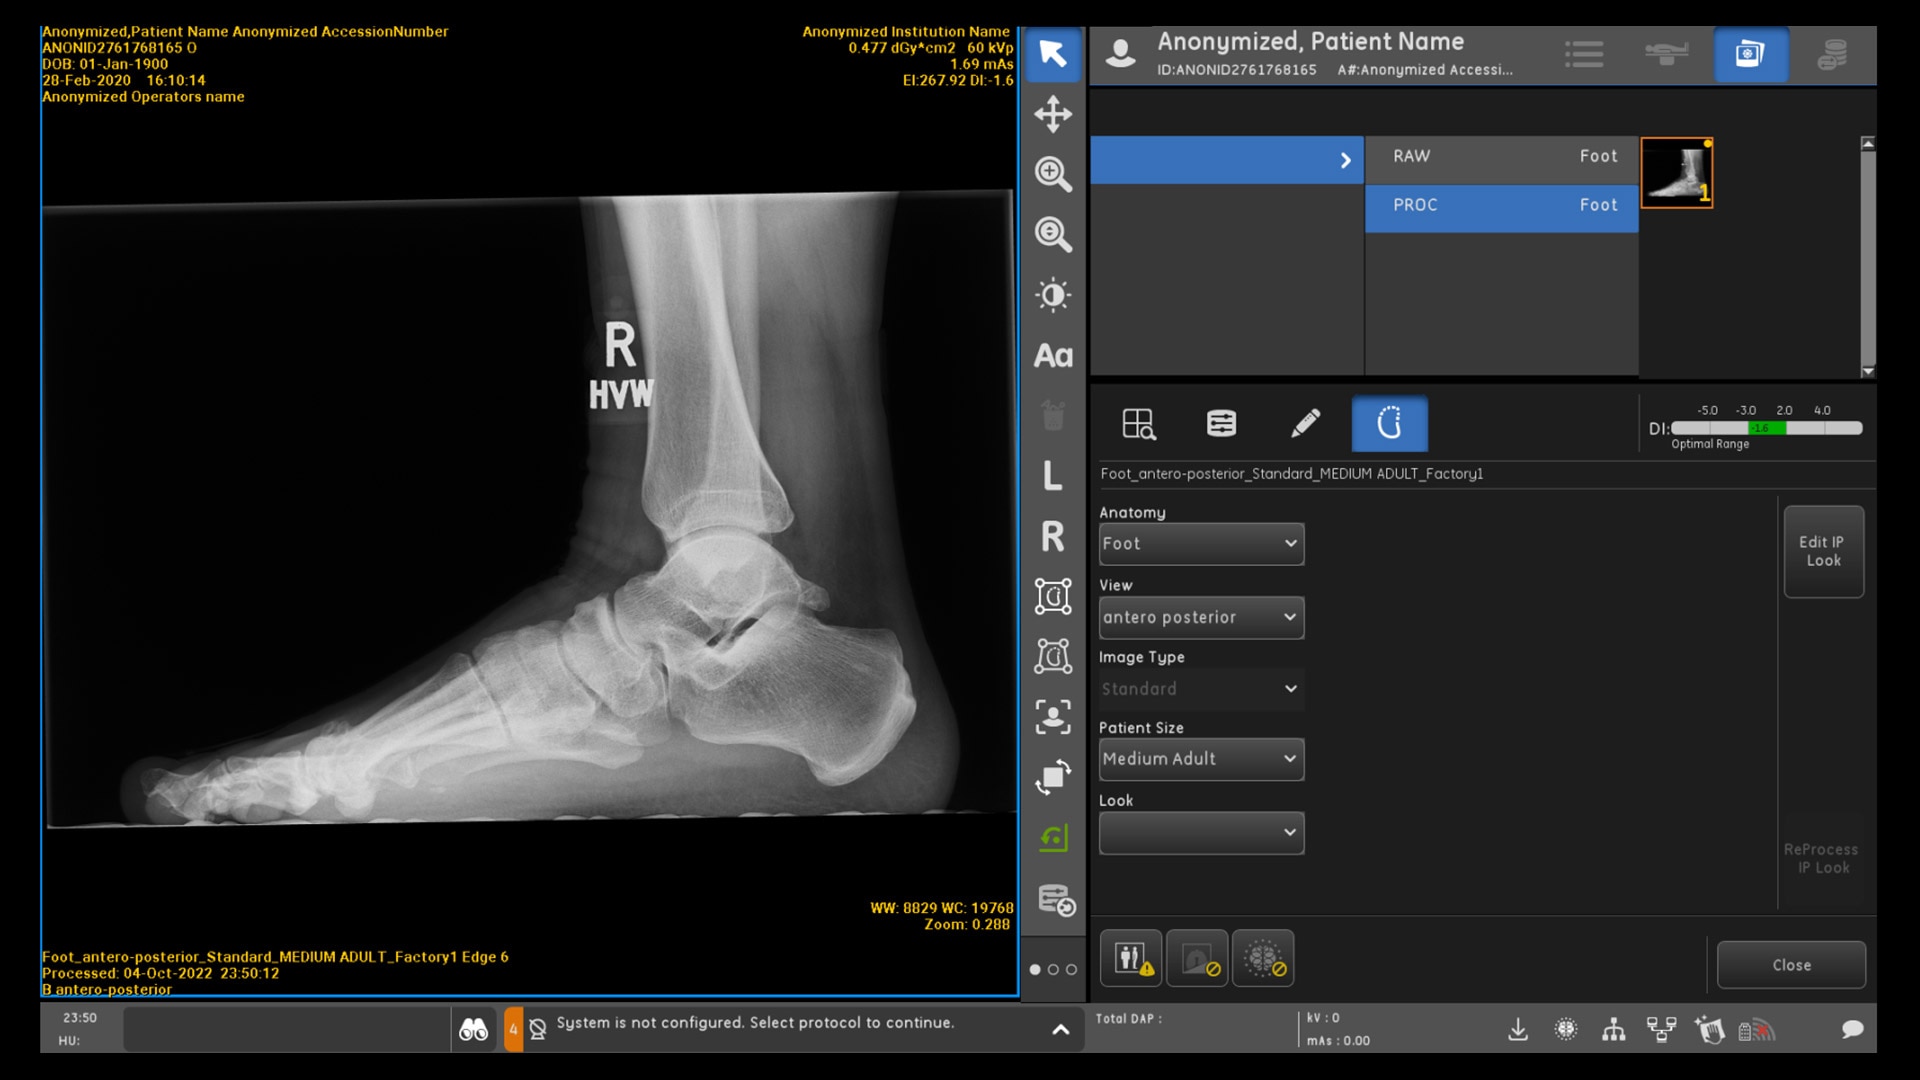

INTELLIGENT PROTOCOL CHECK

AI that helps detect improper protocols

Intelligent Protocol Check conducts an automated quality check to detect errors on the acquisition system, such as a mismatch between the protocol used and the anatomy that was acquired.2 The system assists technologists by notifying them of the mismatch, allowing corrective action to be taken.

Quality care suite feature hero intelligent protocol check